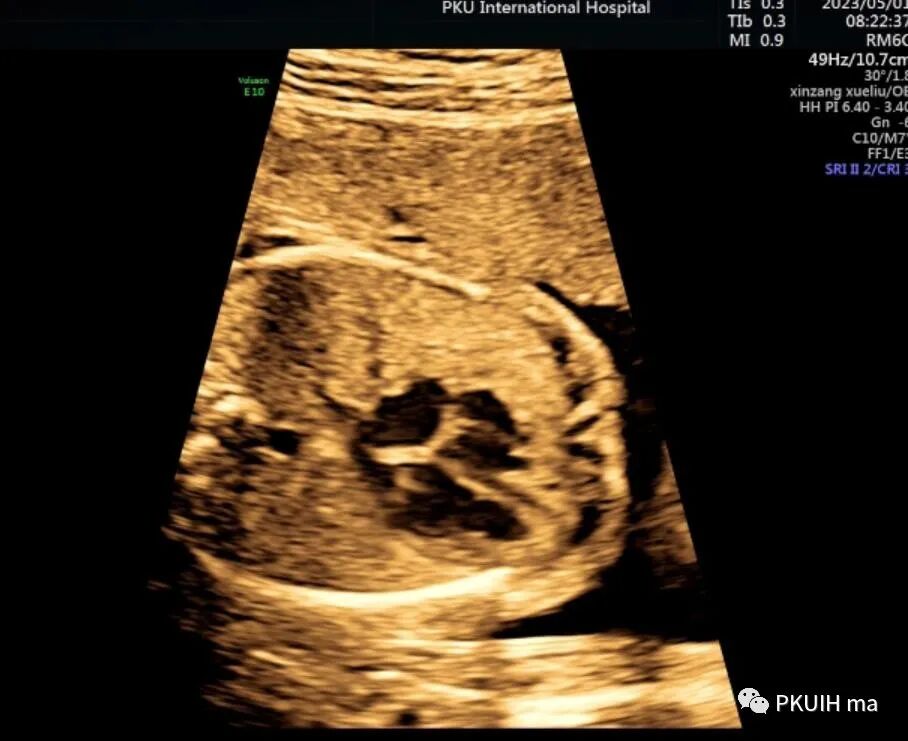

胎儿心脏大部分位于右侧,心尖指向右前方,左房位于脊柱前方,右室位于胸骨后方,右室心尖部可见调节束,心室–大动脉连接关系正常,整个心脏呈镜面右位心。